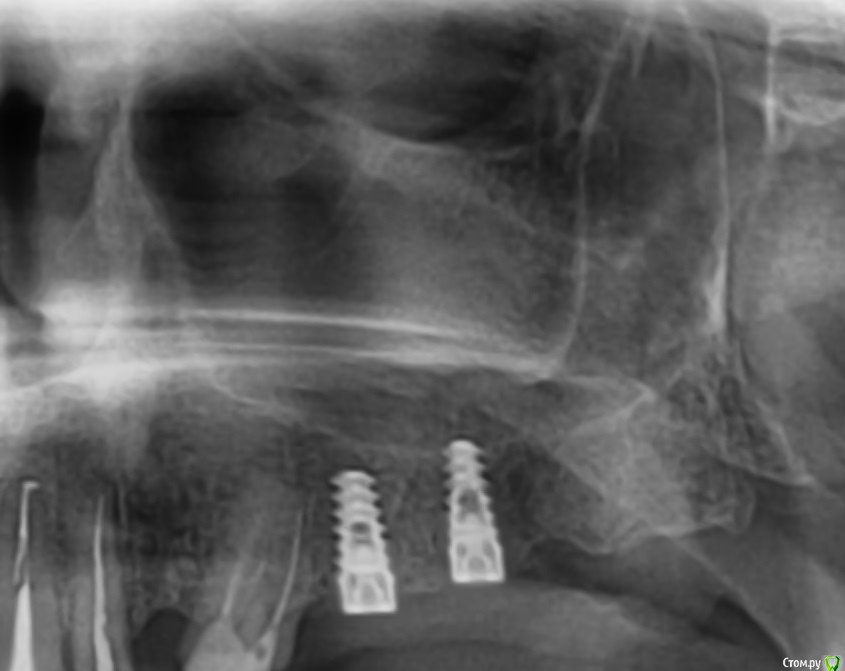

ileanacosanzeana Опубликовано 12 января, 2017 Поделиться Опубликовано 12 января, 2017 Перфорация Гайморовой Пазухи? Ссылка на комментарий

Bier Опубликовано 15 января, 2017 Поделиться Опубликовано 15 января, 2017 там нет перфорации, над имплантатом видна кость. Т.е. врач прямо кончиком имплантата поднял дно пазухи. Все хорошо у вас. Ссылка на комментарий